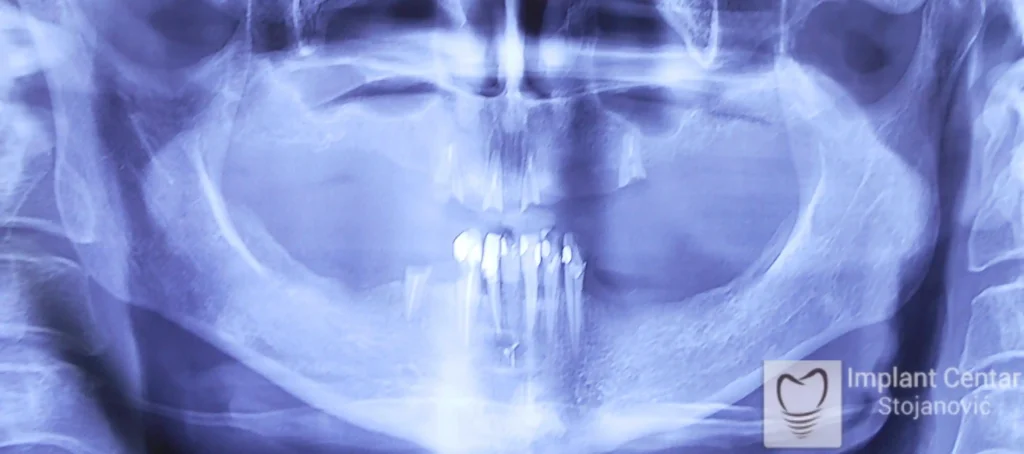

Na slici 1. i slici 2. prikazan je izgled pacijenta pre početka terapije – klinički i rendgenološki.

Nakon vađenja zuba, ugrađeni su implantati. Na slici 3 prikazan je ortopan snimak sa ugrđenim implantatima. Tokom perioda osteointegracije, pacijent je bio zbrinut fiksnim privremenim krunicama na implantatima, koje su izrađene samo dva dana nakon hirurške intervencije.